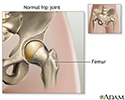

Your hip joint is made up of 2 major parts. One or both parts may be replaced during surgery:

- The hip socket (a part of the pelvic bone called the acetabulum)

- The upper end of the thighbone (called the femoral head)

Diseased hip - illustration

Diseased hip

illustration